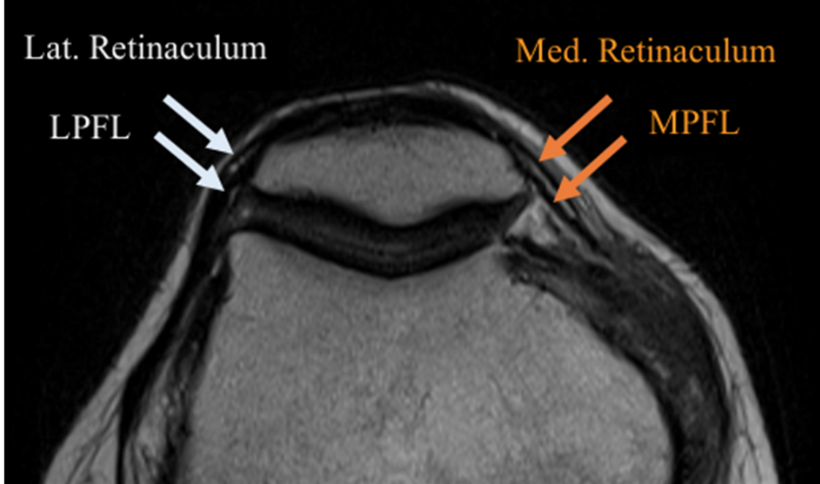

Medial Patellofemoral ligament (MPFL)

• Thicker deeper dark line

• The more superficial, thin and whispier line is the medial retinaculum